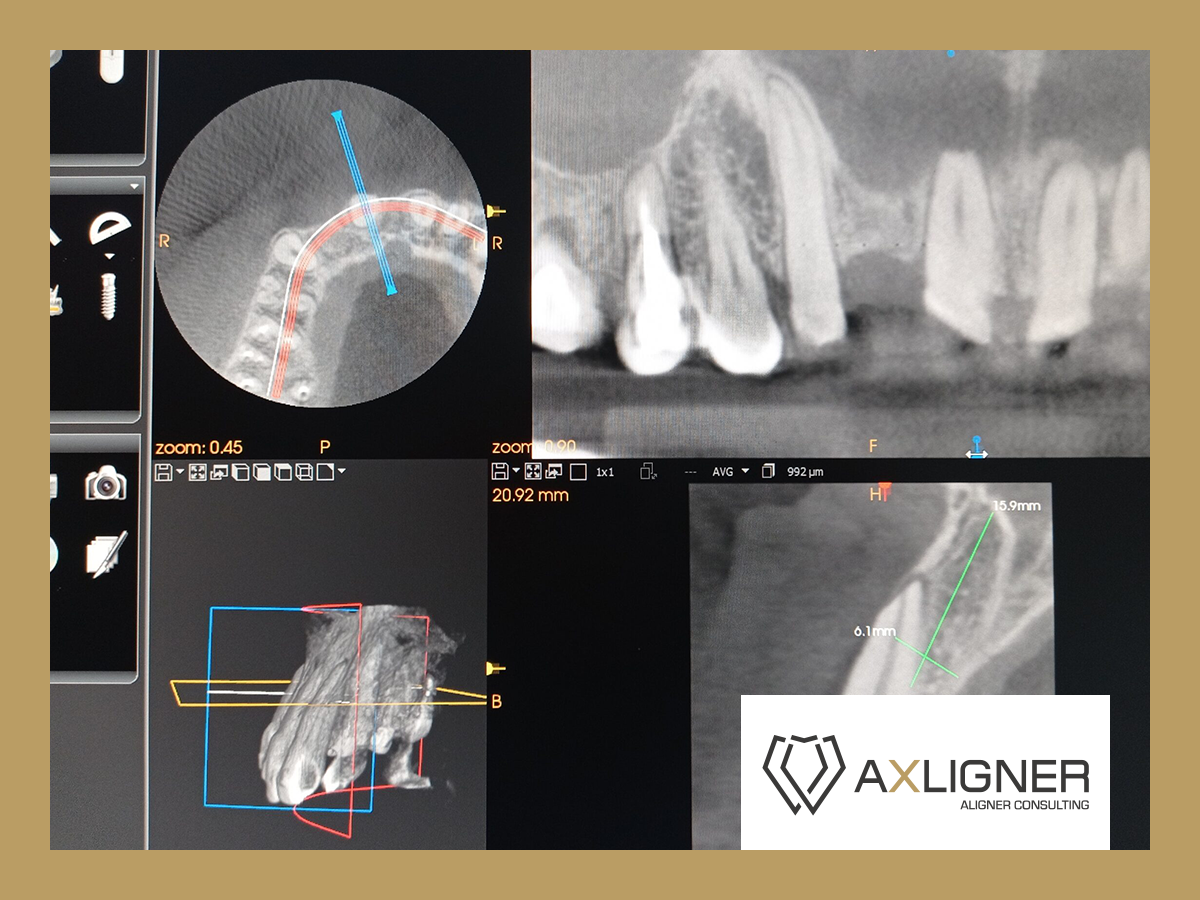

Konsultacja zawierała analizę Cyfrowego Planu Leczenia, którym był leczony pacjent. Na dodatkowe zlecenie lekarza przeprowadzono częściową analizę badania CBCT, zdjęcia panoramicznego, cefalometrycznego oraz zdjęć fotograficznych wewnątrzustnych przed i po leczeniu.

Wykonano ewaluację zaproponowanych sekwencji ruchów zębowych w dostarczonym planie 3D. Wzięto pod uwagę liczne przyczyny mogące doprowadzić do dehiscencji kostnej w omawianej okolicy, jak również przeanalizowano możliwość jej obecności jeszcze przed podjęciem leczenia. Odpowiedziano na wszystkie pytania dentysty w formie pisemnej oraz ustnej.

Wybrane ryciny z konsultacji